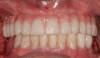

Implant Position Critical to the Restoration

Some of the most complex restorative and surgical patients treated in implant dentistry involve single and multiple implants in the esthetic zone. Thicknesses of crestal and buccal soft tissues and buccal and palatal cortical plates, buccal-lingual ridge dimensions, proximity to adjacent teeth, implant-to-root relationships, gingival and papilla support and contours, gingival exposure, smile lines, and implant angulations and emergence are a few of the many complex considerations.

An important prosthetic consideration is knowledge of the appropriate implant position based on the type of restoration planned (cement- or screw-retained). Small variations in implant positions can lead to difficult restorative dilemmas. Accurate and predictable implant positioning using guided implant planning and placement can be critical to the esthetic and functional success of the restoration30 (Figure 8 through Figure 11).